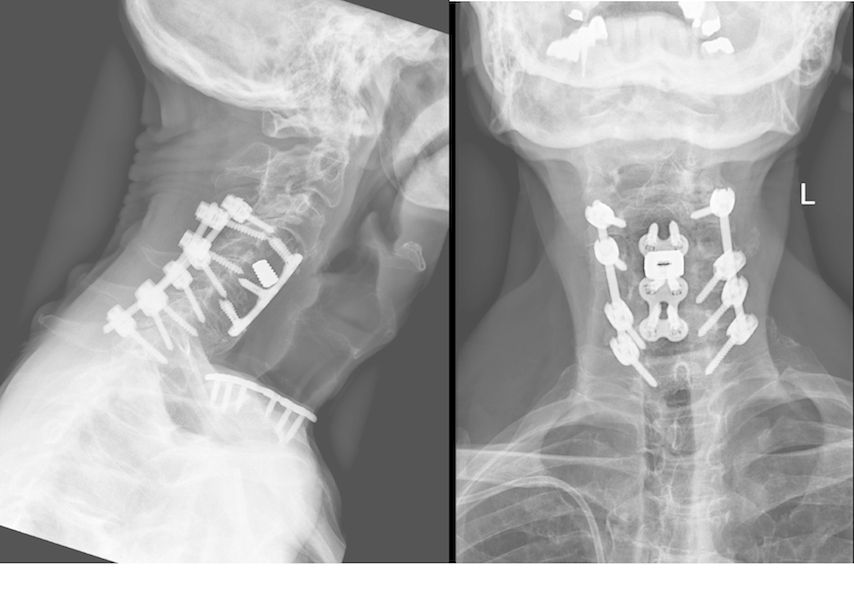

Fallbeispiel 1

Beispiel für die Implantation zervikaler Pedikelschrauben. In diesem Fall kam es bei einem 61-jährigen Patienten 10 Jahre nach anteriorer zervikaler Diskektomie und Fusion (ACDF) C4/5 und ventraler Verplattung C4–6 zu einer Ankylosierung auch von C6/7. Nach Sturz kam es zu einer Fraktur bei C6/7 mit begleitender Bogenfraktur und auch Beteiligung der dorsalen Ligamenta (Abb. 1 und 2). Klinisch bestanden ausgeprägte Nackenschmerzen und kein neurologisches Defizit. Es wurde die Indikation der dorsalen Verschraubung von C4 auf Th1 gestellt. Intraoperativ wurde routinemäßig zusätzlich eine kleine Referenzschraube in einer Lamina – entfernt von der Dornfortsatz-Referenzklemme für die Navigation – gesetzt. Mit dieser konnte intraoperativ die Genauigkeit der Navigation exakt überprüft werden (Abb. 4 und 5). Mittels navigierter High-Speed-Fräse wurden die Schraubenkanäle vorgebohrt (Abb. 6), im Anschluss wurde der Bohrkanal ausgetastet und die Schrauben wurden implantiert. Abbildung 7 zeigt eine Röntgenkontrolle 3 Monate postoperativ.